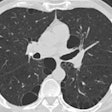

Emphysema-related COPD on CT signals higher malignancy risk

January 17, 2016